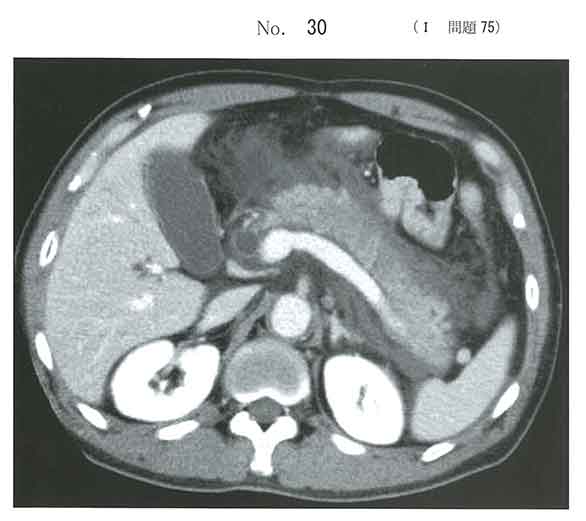

b

筋性防御でc選んだけど、輸液が先だよなぁ

輸液が先っていうか急性膵炎の状態で手術しないんじゃないの

感染を伴えば手術はやりますが、bが正答。